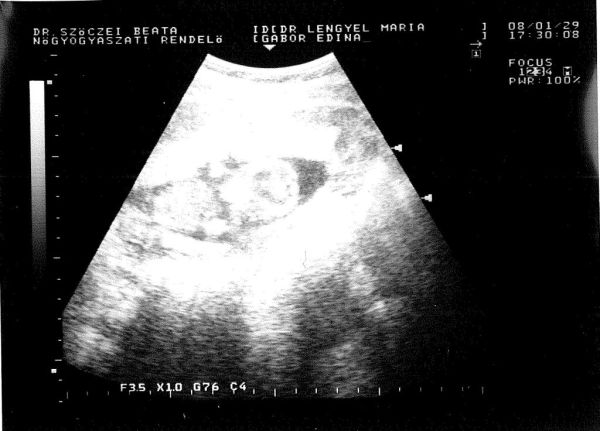

Lezajlott a tegnapi UH, picurka nagyon aranyos volt. Készségesen mutogatta magát, rúgkapált, és közben a fejét fogta mindkét kezével :lol: Majdnem megzabáltam olyan tündér volt.

Sajnos méretet már nem tudott neki mérni a doki néni, okát persze nem értettem, de a többi méret (fej, comb stb) azt mutatja, hogy 14+1-nek felel meg, azaz a könyvem alapján 8-9 cm-re tehető.

Na a képecskét megkaptam, elég rossz a minősége, mert hasi UH volt, bent a főnököm bescannelte, de nem jpg lett, hanem pdf. Nem is ezzel van a baj, hanem hogy a kép kicsi, és rengeteg fehér semmi veszi körül, így nem túl élvezetes.

Ja, és a lényeget majdnem kifelejtettem... nagyon fiúnak mutatta magát :lol: Volt valami a lába között, több nézetből is megnézte a doki néni, mondta, hogy szerinte fiú, de azért még ne vegyek rá mérget, mert esetleg a köldökzsinór is lehet...na azóta fülig ér a szám :lol:

Pöttömpanni babája:

Kép

Nem lett tökéletes, nézzétek el nekem! :oops:

Lányok íme a pacám lásd fentebb :lol:

Annyi kivehető, ahogy a fejét fogja, úgy sopánkodik :lol:

érdekes, mert sok olyan kép van, amin nem mindig tudom egyből, hogy mi hogy van, de ezen a képen egyből láttam, hogy a fejét fogja a kezeivel :)

Na kollégám is alkotott egyet, nem tudom ez milyen:

beszkenneltük tifben is így úgy látom jobb lett, de szegényt ebédről rángattam a gépem elé :lol:

ezen is jól látszik :)

Én az elsőn nem láttam, de ezen már igen. Nagyon aranyos.

Bocs, de ezen tényleg jobban látszik ;-) nagyon ari :-D